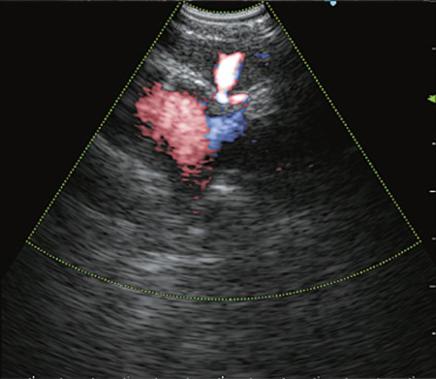

近期,市中心医院内镜中心引进一套日本奥林巴斯新型EVIS LUCERA ELITE CV290电子胃肠镜系统和EU-ME2 Plus超声内镜诊断仪,作为目前自治区最先进的内镜设备,它拥有革新的技术,为消化系统疾病的诊断和治疗带来巨大变革。

超声内镜(EUS):即内镜和超声相结合的消化道检查技术,将微型高频超声探头安置在内镜顶端,当内镜插入体腔后,在内镜直接观察消化道黏膜病变的同时,可利用内镜下的超声行实时扫描,可以获得胃肠道的层次结构的组织学特征及周围邻近脏器的超声图像,从而进一步提高内镜和超声的诊断水平。

简单来说,医生在使用超声内镜进行检查时,发现病灶,可直接诊断病变的起源层次,并可根据大小、回声特点等初步判定肿瘤性质,是生理性改变还是病理性改变,是器质性改变还是功能性改变等等。

电子凸阵扫描

电子环形扫描

PowerFlow模式

ColorFlow模式

H-Flow模式超声内镜的展望

随着超声内镜技术在临床的普及,其应用越来越广泛,尤其对于消化道肿瘤的术前分期,明确消化道早癌的浸润深度,合理把握内镜下微创治疗的适应症起到重要作用。有了超声内镜这一有利武器,使得许多疑难复杂的消化系统疾病的诊断和治疗变得容易,从而使市中心医院对消化系统疾病的诊治迈上了一个新台阶。